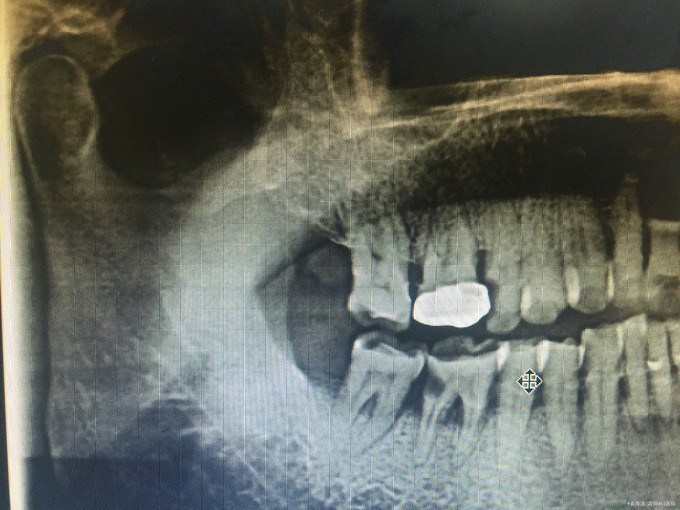

临床检查:46牙合面无明显龋坏,远中邻面食物嵌塞探疼(+),冷(++),叩(-),松动度(-),牙周红肿。 辅助检查:X线示46远中邻面龋坏累积髓腔,根尖周牙周膜增宽。

诊断:46牙髓炎 治疗:经患者知情同意后,46局麻去腐降牙合,开髓拔髓寻找根管口,建立直线通路,扩通根管,确定工作长度。S3/EDTA凝胶镍钛器械,低浓度次氯酸钠冲洗根管,预备至25/06,氢氧化钙诊间封药,一周后复诊,试主尖X线示恰充,试干根管,导AH-PLUS糊剂,VDW热压胶垂直加压根充,术后见根管恰充,暂封调合抛光。桩冠修复。